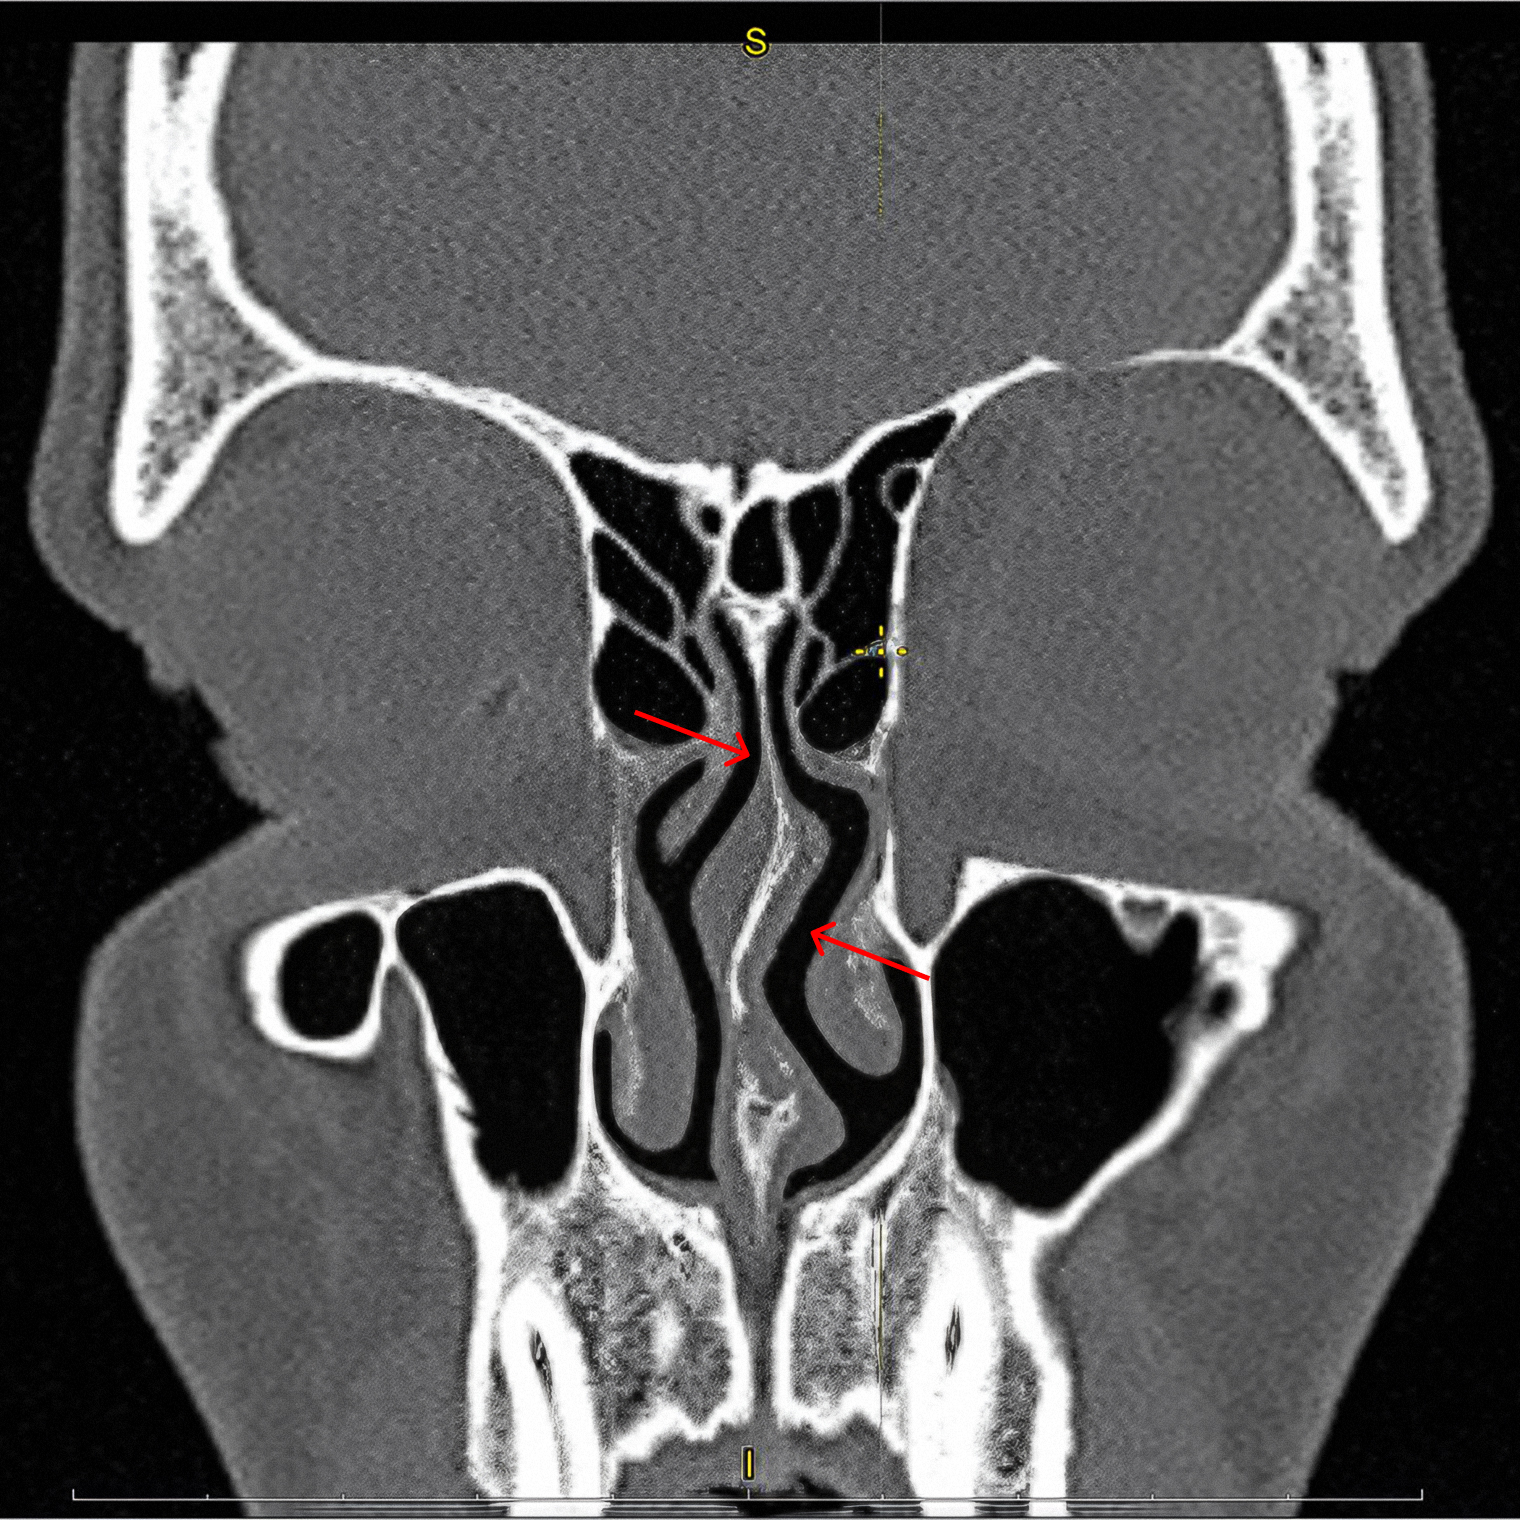

Операцию на носу запланировали через несколько месяцев. За это время нужно было пройти КТ пазух носа, ЭКГ и флюорографию, сдать анализы крови и мочи, получить допуски стоматолога, терапевта и лора.

| КТ носа | 3 000 ₽ |